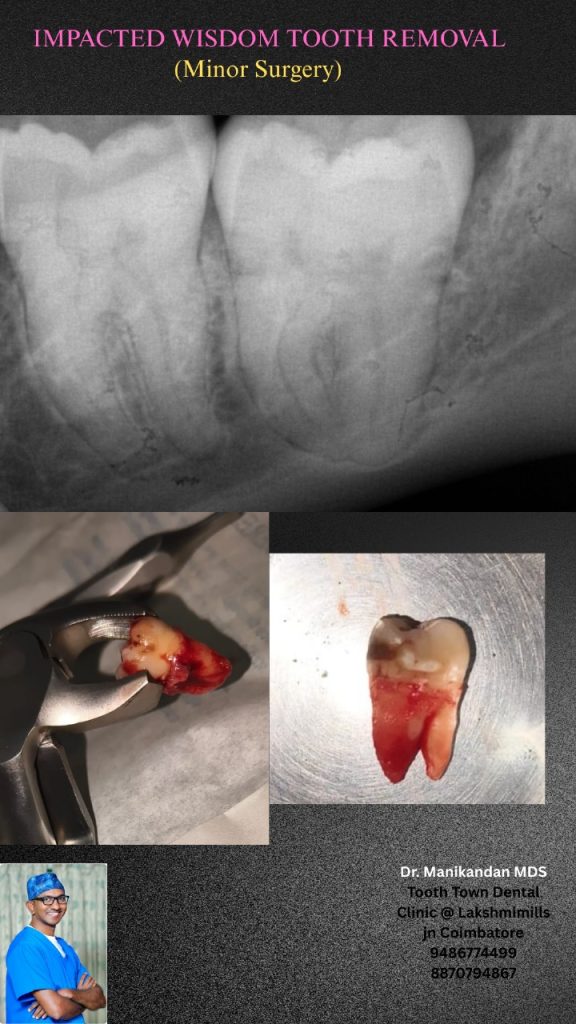

Wisdom tooth extraction

Wisdom tooth extraction involves numbing the area with anesthesia, making an opening to access the tooth, and then removing it. The tooth may be divided into smaller pieces for easier removal, and any bone blocking the access to the wisdom is also removed if needed. The site is then cleaned, micro sutured (if necessary), and packed with cotton gauze to help stop bleeding and promote clotting.